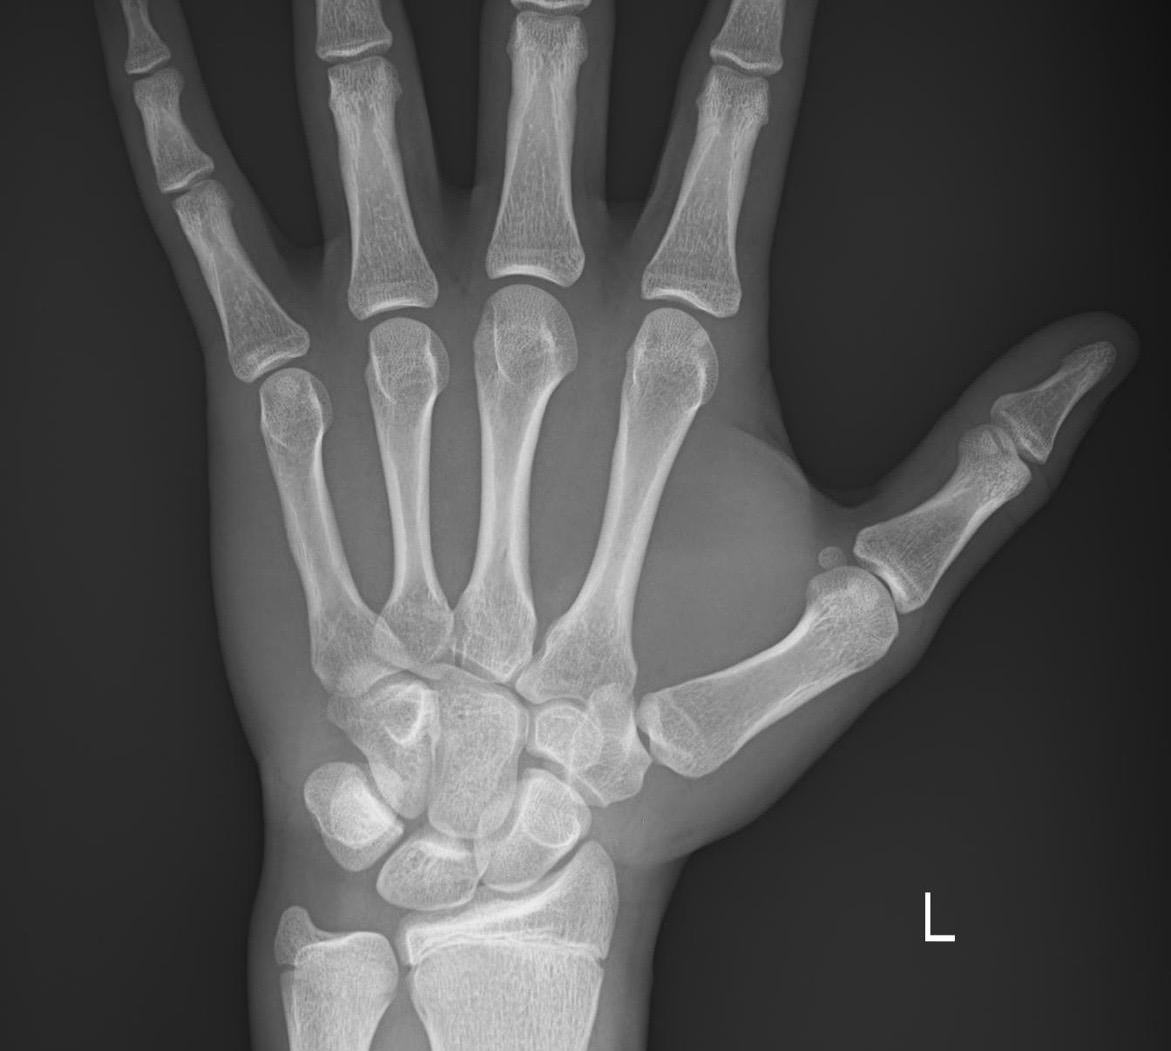

Is it worth taking hgh and an ai or is it too late to have meaningful change? I’m 16 it has been like 4 months since this was taken

Bro I put an image 😭. Pretty sure when I got it the doctor said I had max 4cm left at time of x ray and it has been 3 months not seen any I don’t think. Are you claiming that hgh is general doesn’t work? Or was it case specific to my bone age?